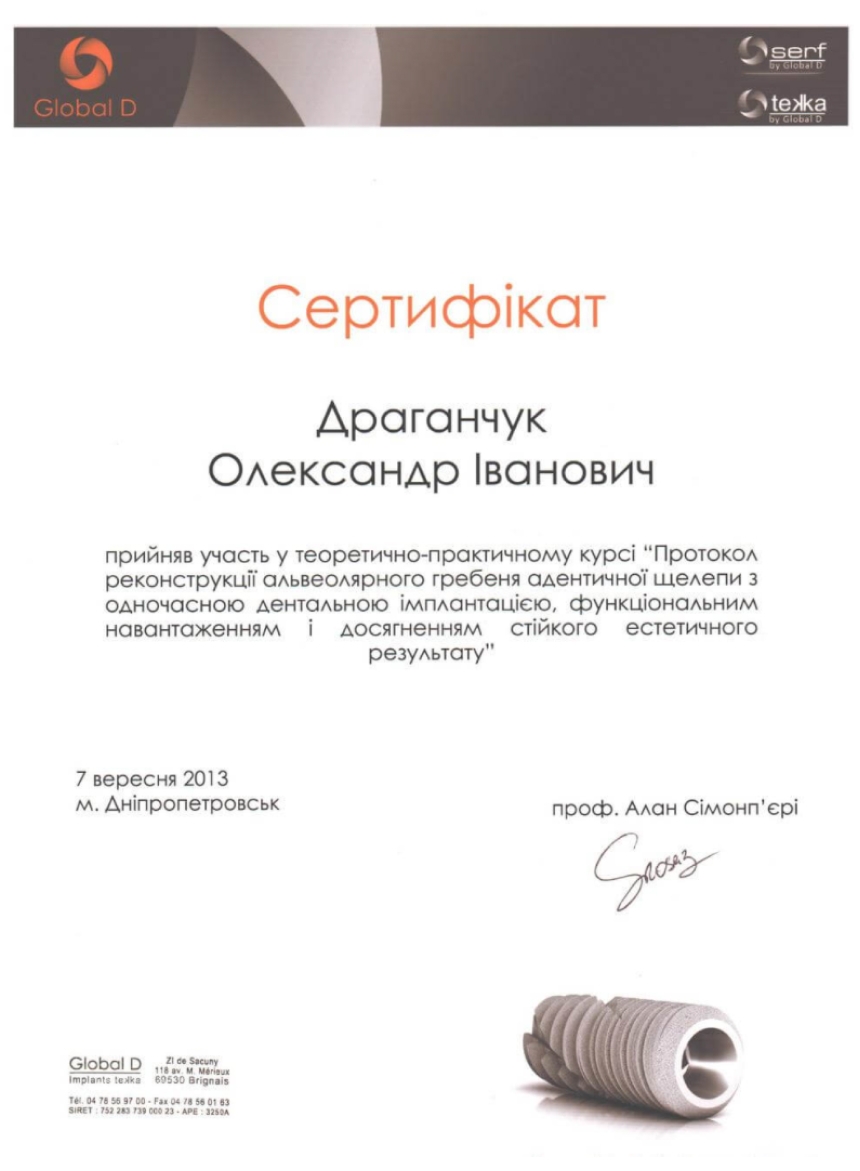

Ми пропонуємо тобі усю стоматологію в одній клініці. У нас ти отримаєш кваліфіковану стоматологічну допомогу: лікування і пломбування зубів та кореневих каналів, послуги з протезування, імплантації та стоматологічної хірургії. Космічна стоматологія Драганчука, це досвідчені фахівці, які навчались та стажувались в Берліні, Парижі, Вільнюсі та Будапешті, найсучасніші та найінноваційніші матеріали та обладнання.